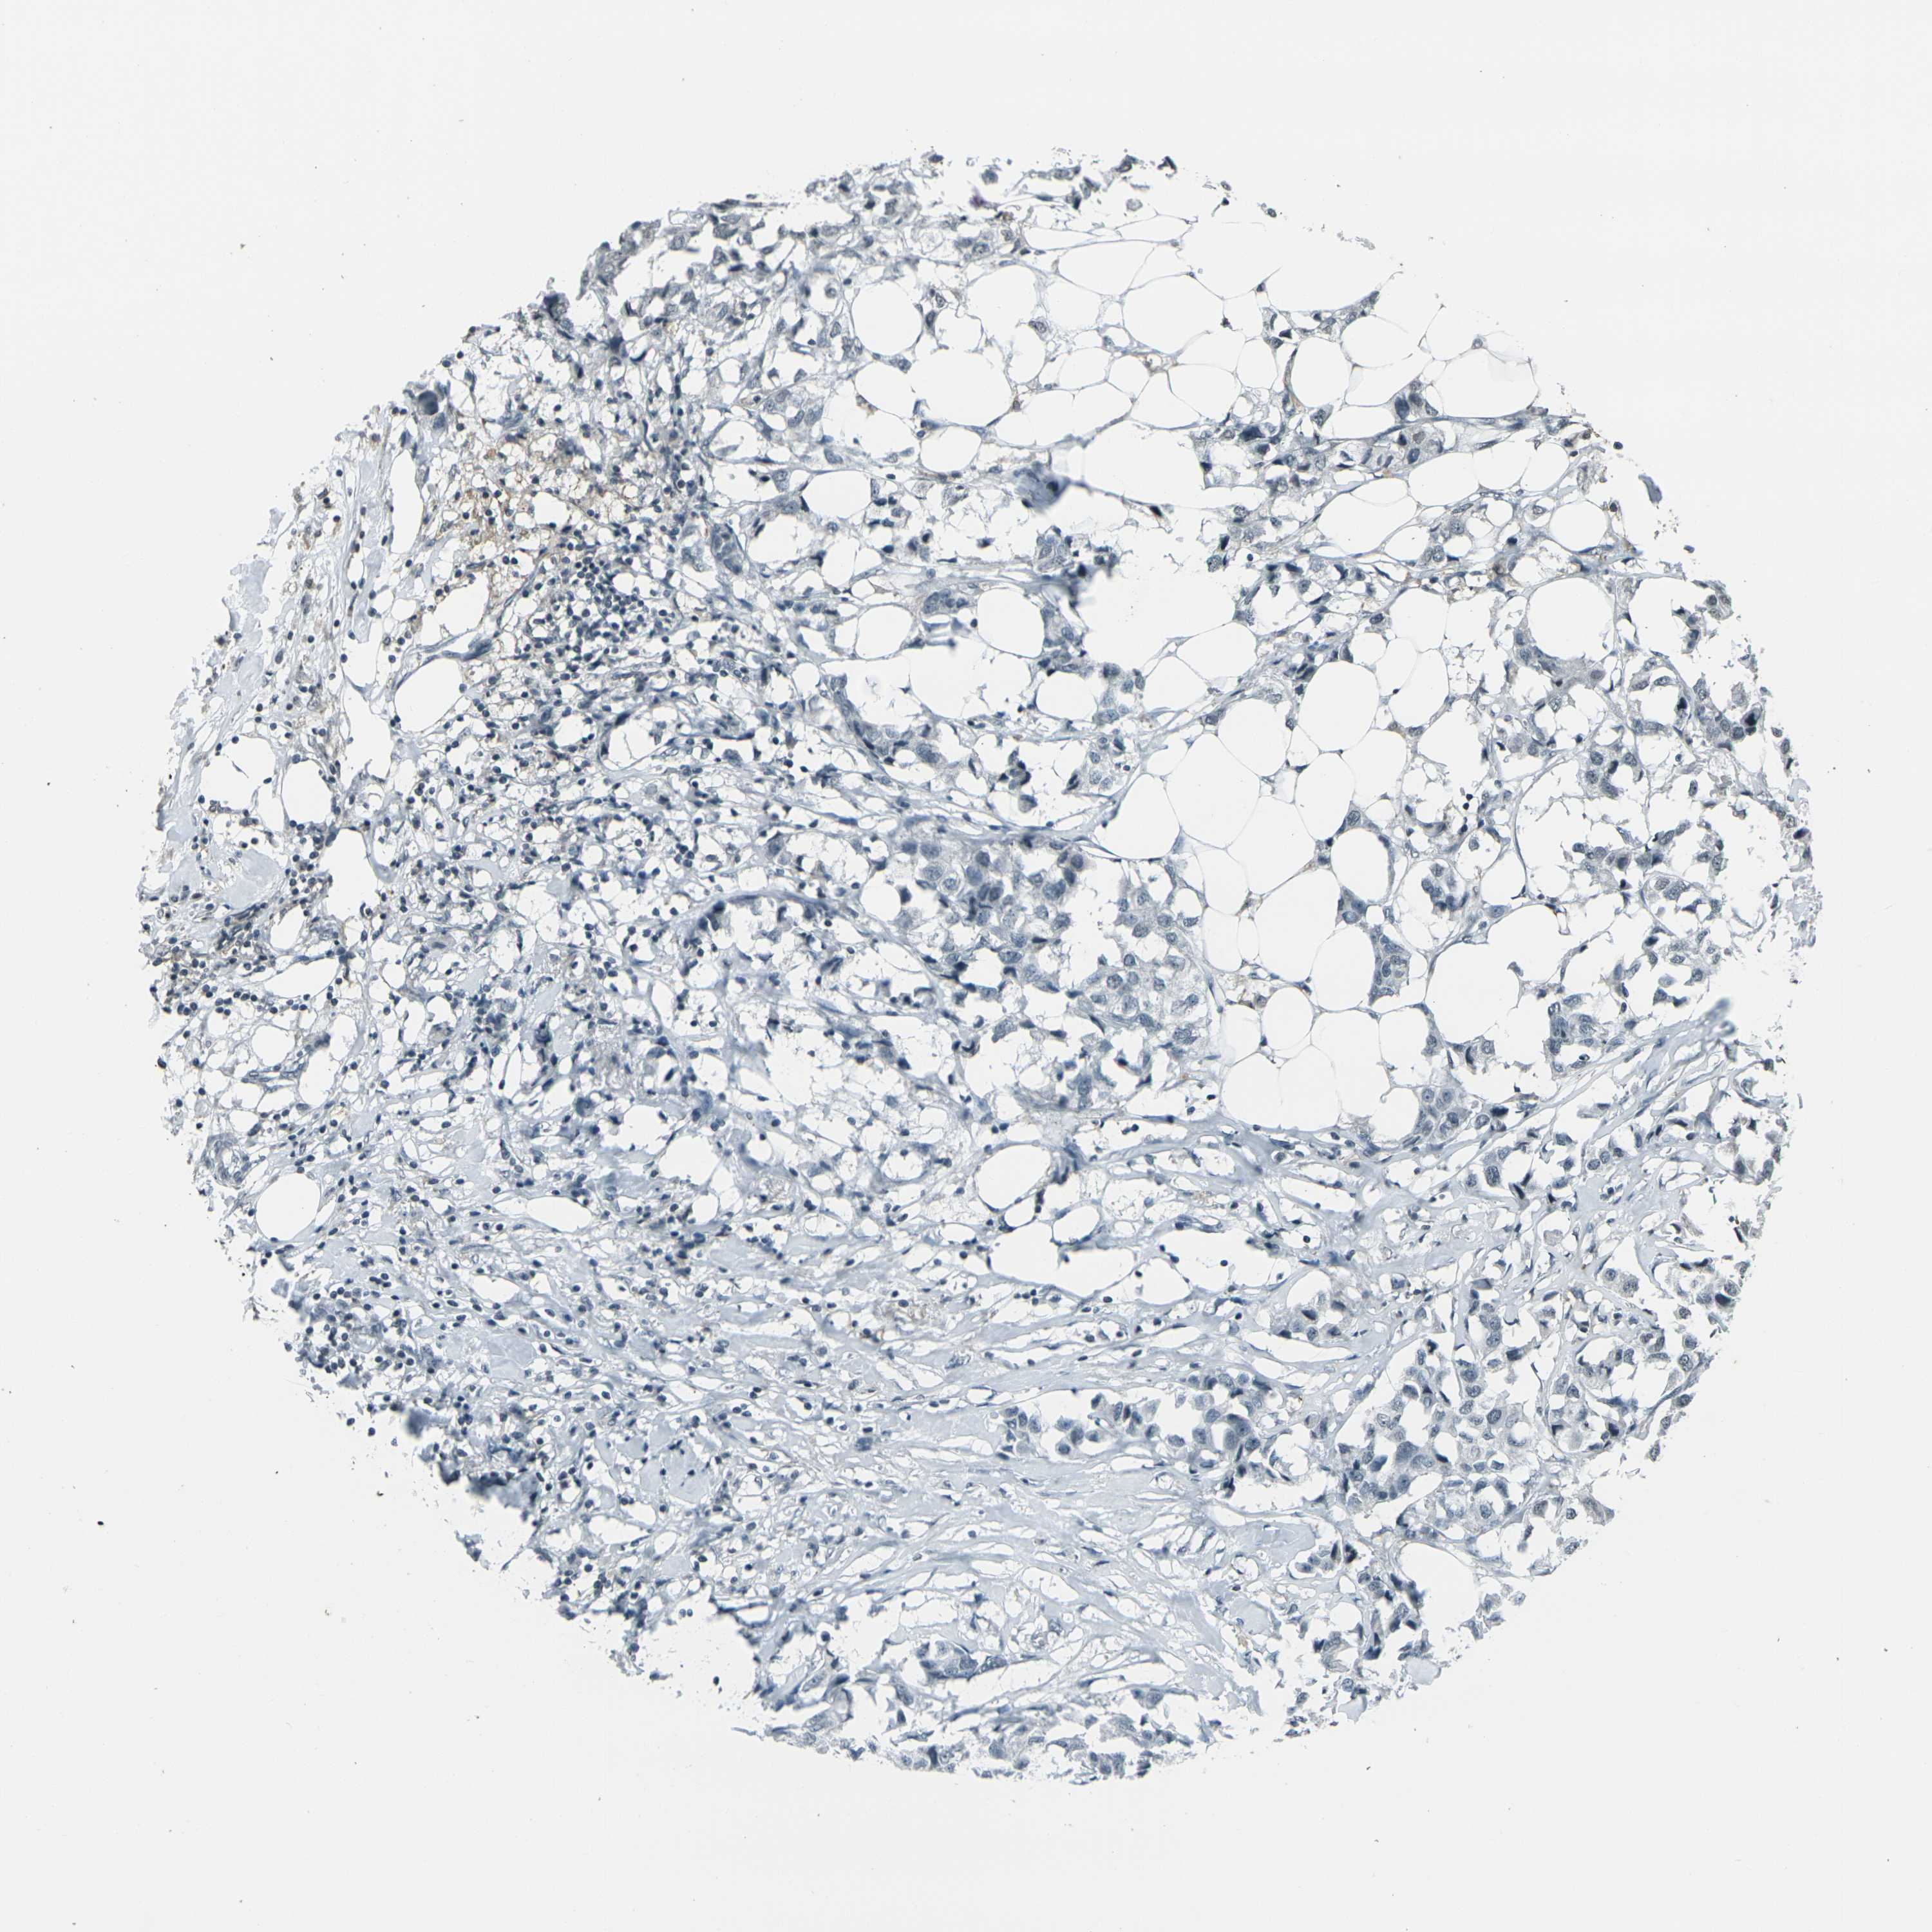

CANCER BREAST CANCER Show tissue menu

BRCA TCGA BRCA VALIDATION PROTEIN EXPRESSION